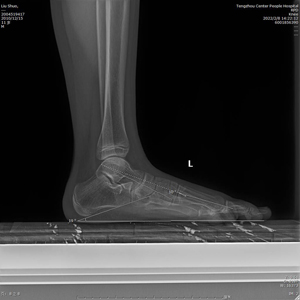

患者少年男性,11歲,因左足弓塌陷并內(nèi)側(cè)疼痛不適1年收入院。張亞州、范明生主治醫(yī)師為患者完善術(shù)前檢查,嚴(yán)格術(shù)前查體,診斷為左足平足癥并左足副舟骨痛。

術(shù)前X線示:左足平足并副舟骨。患者經(jīng)過足跟墊等保守治療效果不佳,潘維亮主任醫(yī)師主持全科醫(yī)護(hù)人員術(shù)前討論一致決定為患者實(shí)施全麻下距下關(guān)節(jié)制動術(shù)。